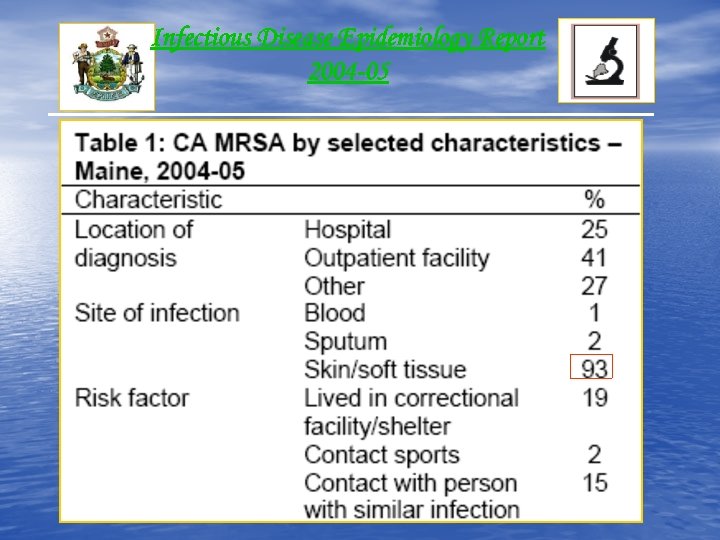

Infectious Disease Epidemiology Report 2004 -05

Infectious Disease Epidemiology Report 2004 -05